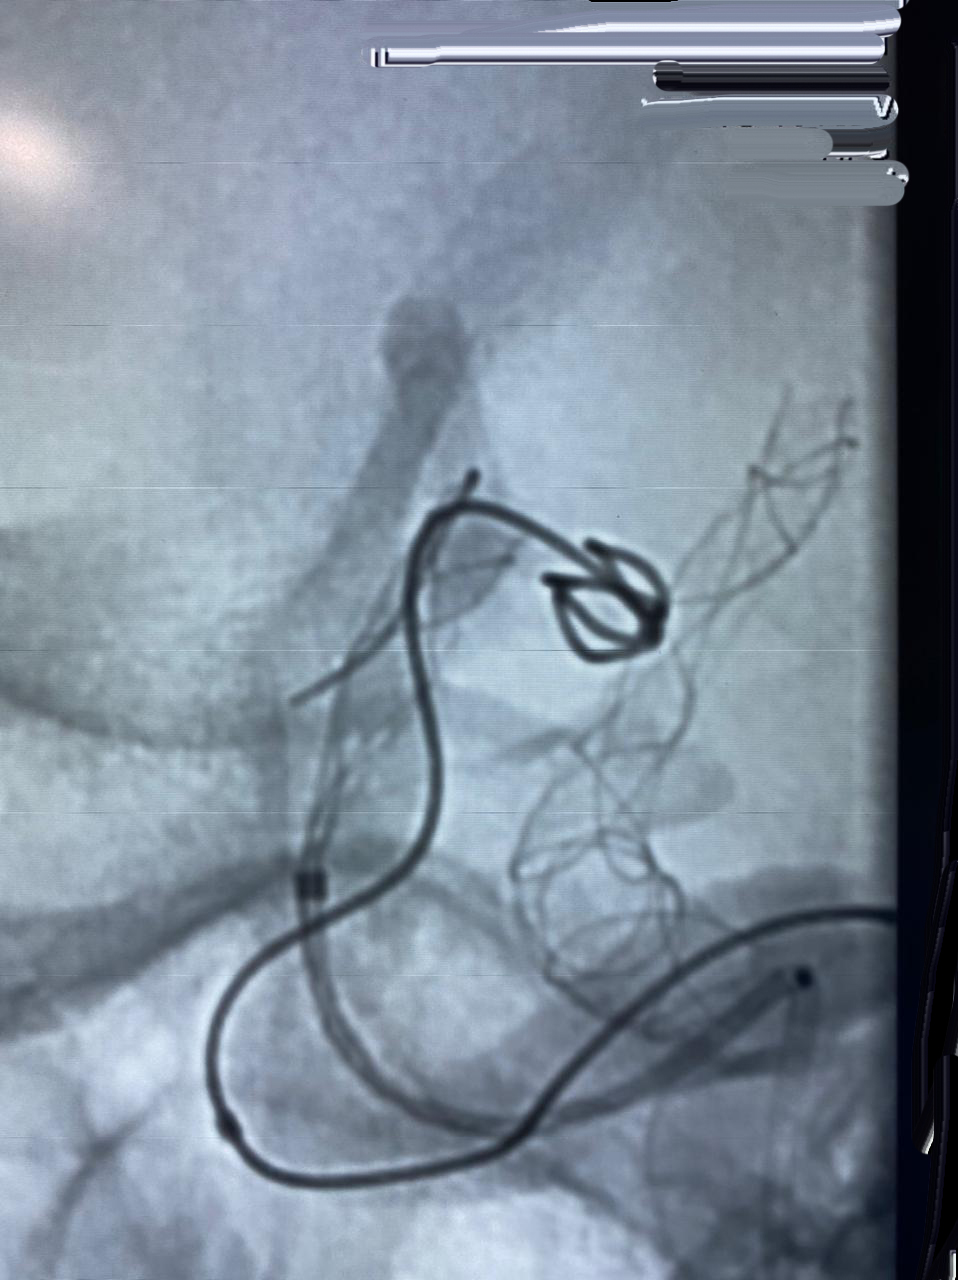

O procedimento de Embolização de Aneurisma Cerebral é realizado no Setor de Hemodinâmica, sob anestesia geral, com um aparelho de imagem de última geração. O tratamento endovascular, é uma opção minimamente invasiva para as doenças cerebrovasculares.

A Neurorradiologia Intervencionista pode ser usada também no tratamento agudo do Acidente Vascular Cerebral (AVC), na doença ateromatosa (entupimento) das artérias carótidas e vertebrais, angioplastia cerebral e implantes de stent e no tratamento de fístulas e malformações arteriovenosas do sistema nervoso central (cérebro e medula).

“O primeiro caso de Embolização de Aneurisma Cerebral em Ponta Grossa, com stent diversor de fluxo, foi realizado no Hospital do Coração Bom Jesus em dezembro de 2018, o HCorBJ tem estrutura excelente para isso, tanto para realização do método, quanto no atendimento pós- operatório dos pacientes na Unidade de Terapia Intensiva (UTI) e enfermaria, com equipes altamente especializadas”, ressalta Sabatini.